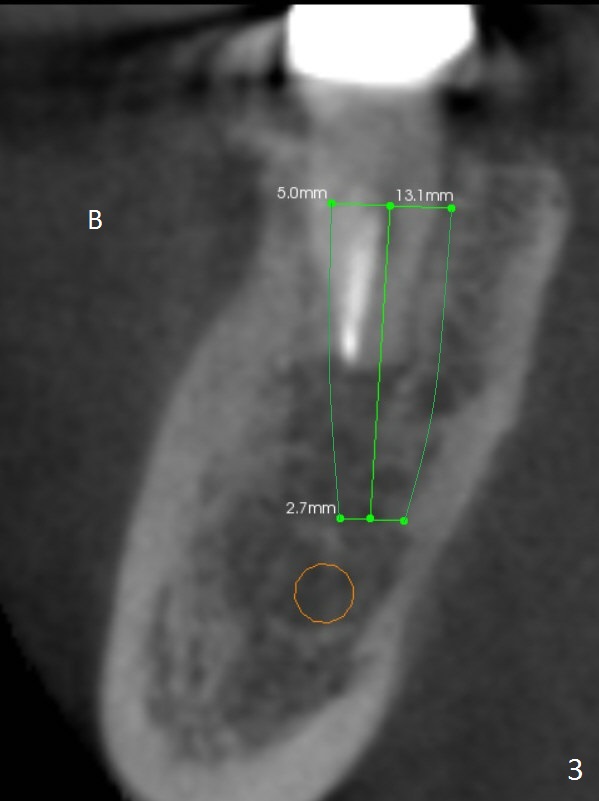

After extraction, the mesial slope of the socket seems to be an ideal osteotomy site (Fig.2 red line) with depth of 15 mm, as suggested by CBCT coronal section (Fig.3).  B: buccal.